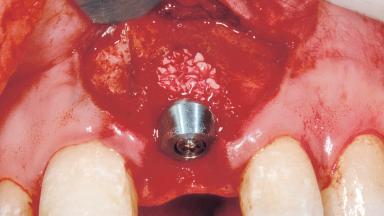

Immediate Placement of an Implant in a Maxillary Left Central Incisor Site

| Bone Augmentation | Horizontal|Simultaneous |

| Augmentation Materials | Xenogenous|Membrane |

| Soft Tissue Grafting | Simultaneous |

| Placement Protocol | Immediate implant placement |

| Socket Integrity | Damage to one or more bone walls |

| Bone Volume | Damage to one or more socket walls |